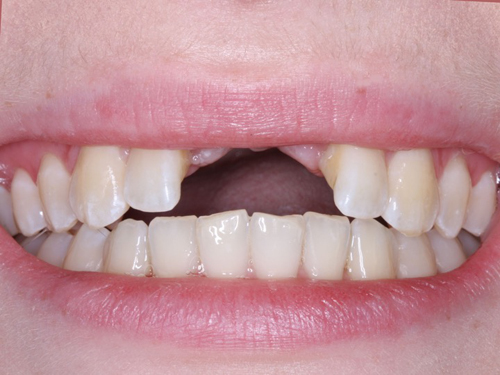

Implants can wear out eventually or without good oral hygiene. Dental implants are not suitable for everyone, few patients may not be eligible for tooth replacement due to their bone health. Dental implants generally require healthy, dense bones. Strong bones in place are a parameter to support dental implants.

Installing a crown is a simpler procedure and requires less time and material to set up. As a result, this is the most profitable option up front. However, a dental implant can last longer than the crown and will not need to be replaced.